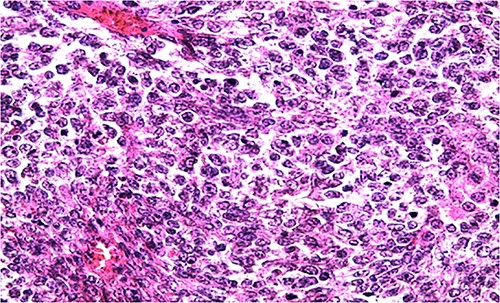

Biologically, the CA 125 tumor marker was at 126.2 IU/ml. The patient underwent a left adnexectomy and an omentectomy (small omentum). Macroscopically, the ovarian mass was smooth on the surface and fleshy on section with the presence of necrotic and hemorrhagic changes. On the histological level, the tumoral proliferation presents a diffuse architecture formed by sheets and clusters separated by fine fibrous septa. Tumor cells are rounded, small, and monomorphic with hyperchromatic, finely nucleolated nuclei and reduced cytoplasm. Mitotic activity is high (36 mitoses/10 HPF) (Figs 3 and 4). The samples taken from the small omentum were tumorous. An immunohistochemical study was carried out and showed diffuse positive expression by tumor cells of Vimentin, and focal by antibodies (Cytokeratin AE1/AE3, EMA, CD99, WT1, Inhibin, and SALL4) and an absence of expression by antibodies (CD45, Chromogranin, PAX8, and AFP) (Figs 5–7).

HE section showing diffuse sheets of small, closely packed round cells with scant cytoplasm separated by fibrous septa (x200).